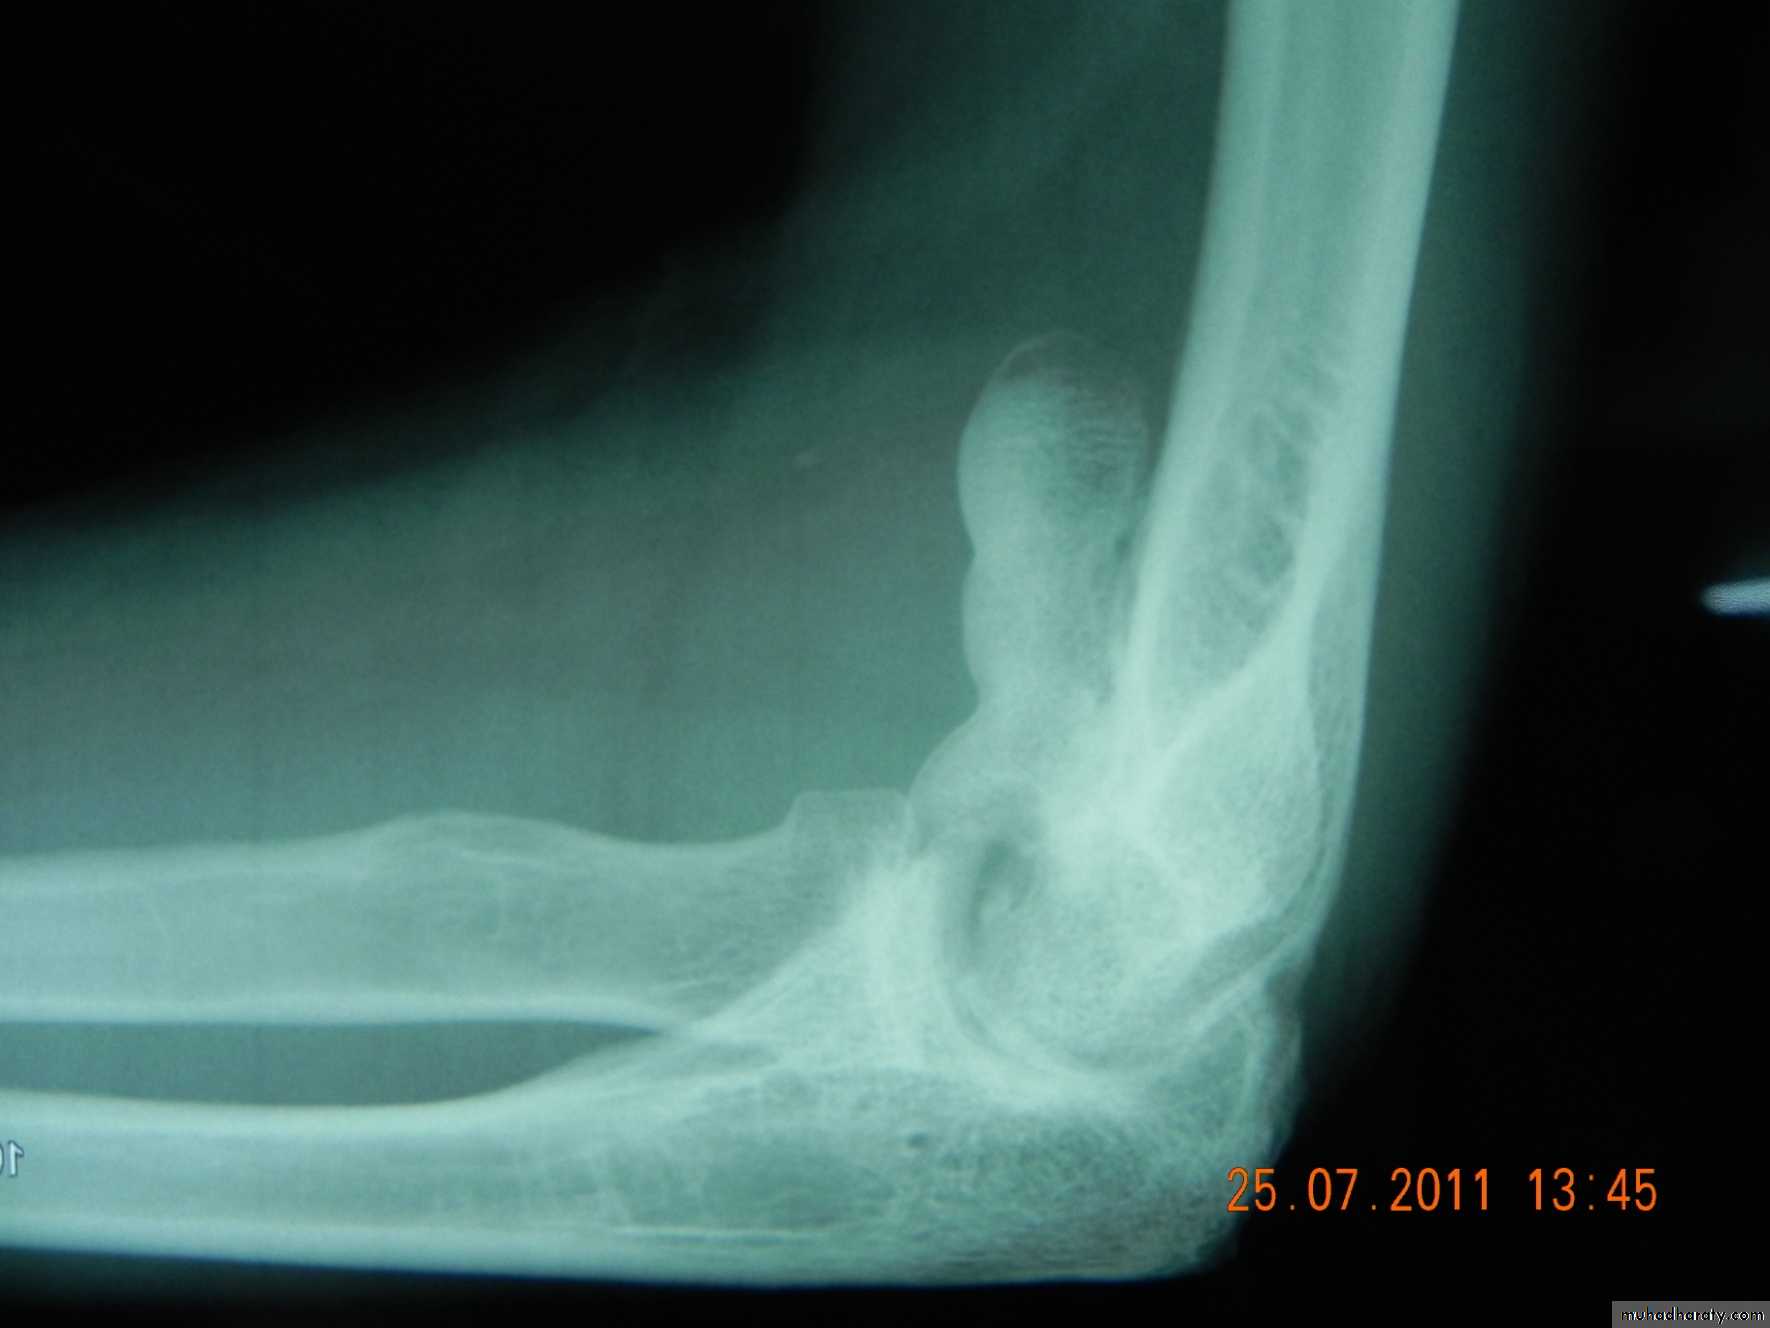

Myositis ossificansJoints